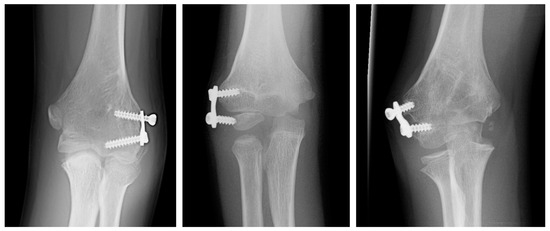

| PRE | POST | Difference | p Value | |

|---|---|---|---|---|

| CA | −20 (−18 to −26) | −6 (−4 to −9) | −16 (−18 to −9) | <0.001 |

| HUA | −19 (−15 to −29) | −8 (−1 to −10) | −16 (−19 to −12) | <0.001 |

| BA | 90 (87 to 100) | 81 (76 to 83) | −11 (−17 to −7) | <0.001 |

| SCA | 29.8 (24.3 to 36.2) | 38.5 (38.1 to 40) | 7.5 (3.3 to 13.8) | <0.001 |

| LCHA | 61.6 (54 to 64.1) | 56.7 (54.6 to 57.3) | −4.8 (−6.8 to 0.6) | 0.018 |